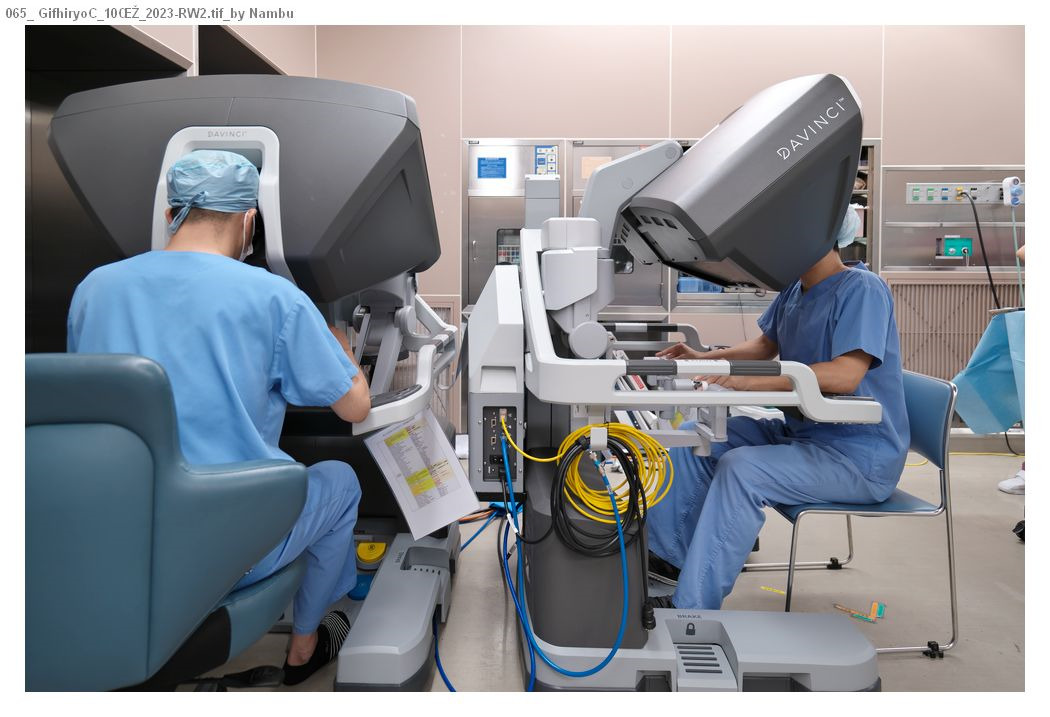

以前は開腹手術が行われていましたが、現在では小さな手術創で体にやさしい腹腔鏡下手術やロボット支援下手術が主に行われるようになりました。これらの手術法により出血量の少ない精密な手術が可能になりました。美容的に優れているだけでなく、術後早期から食事が開始でき、早く退院できる(術後7~14日)ことや術後の腸閉塞が起こりにくいことなどの利点があります。

ロボット(ダビンチXi)支援下直腸切除術の実際